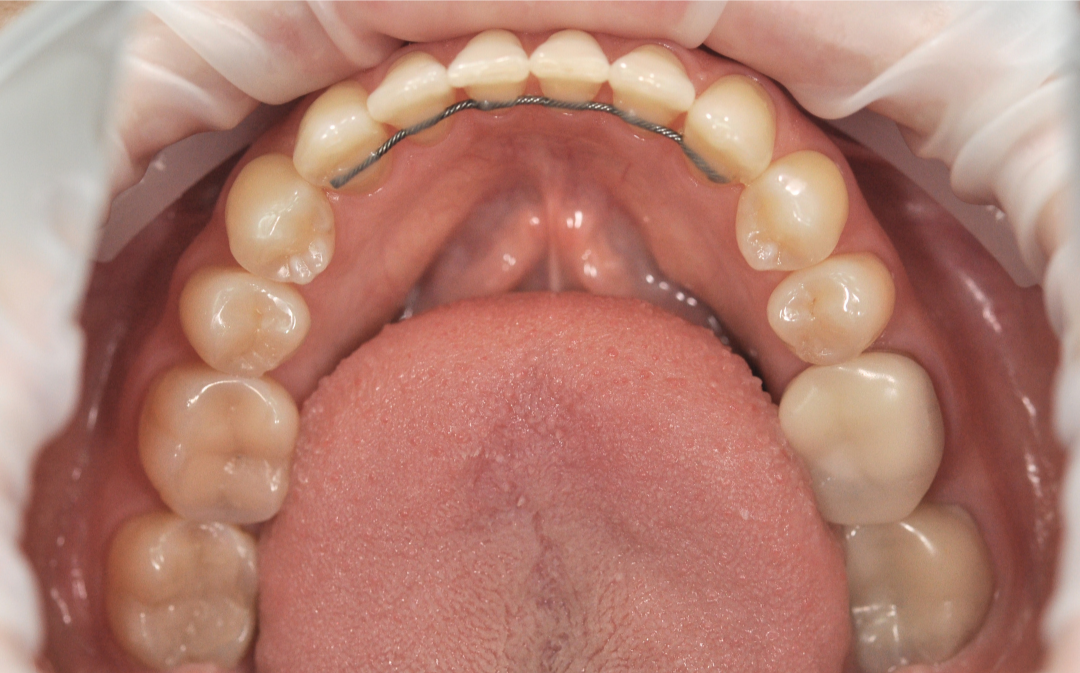

Этап №4

Финишная реставрация.

После снятия брекет-системы стоматолог-терапевт провела художественную реставрацию формы боковых резцов, добившись идеальной гармонии и естественности улыбки.